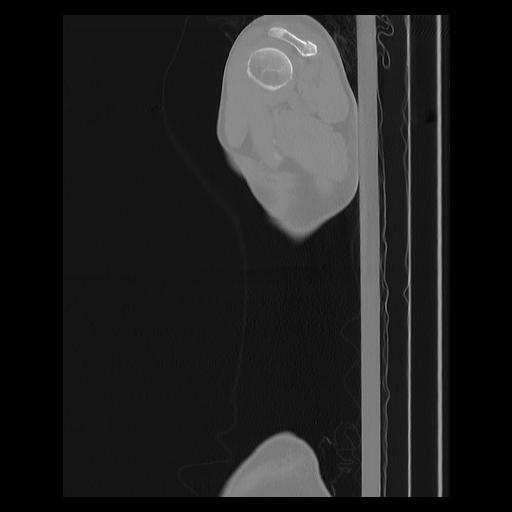

33 PULMON,CE,Sagittal,3.000,PULMON,Sagittal,